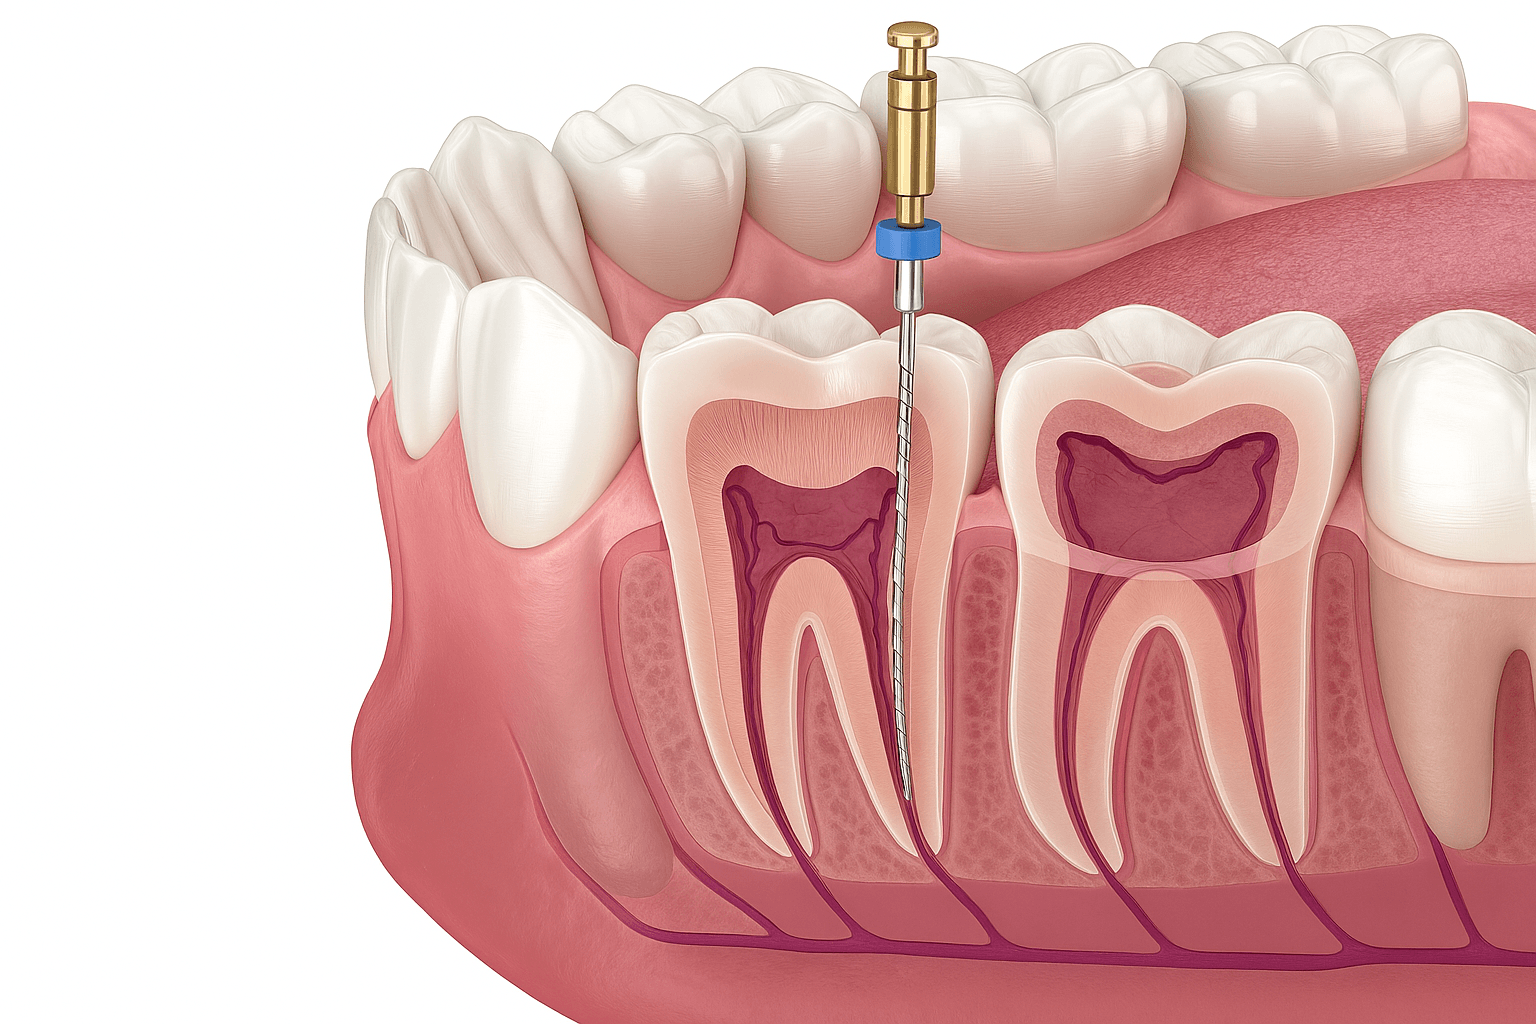

- • Proces leczenia obejmuje diagnostykę, zabieg chirurgiczny, gojenie oraz zamocowanie korony, mostu lub protezy.